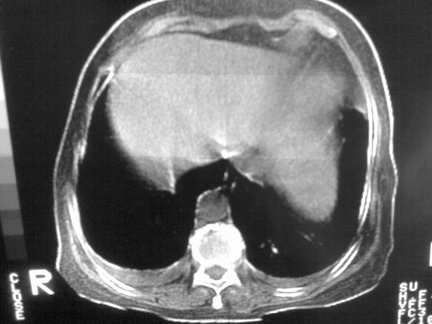

标题: CT13142:女 80 胸闷、气短、1w [打印本页]

标题: CT13142:女 80 胸闷、气短、1w

双侧胸腔积液

胸膜肥厚,

右肺感染;双侧胸腔少量积液,心影增大,可能与心功不全有关;胸内甲状腺肿。

胸内甲状腺肿;右肺感染;双侧胸腔少量积液。

胸内甲状腺肿;右肺中叶感染;双侧胸腔少量积液;心影增大,考虑有心功能不全。